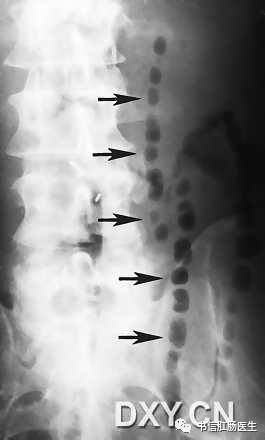

2.珠链征(串珠征)

★ 图示小肠梗阻患者,左侧卧位。气泡(箭头)为环状皱壁间的气体潴留。

■ 影像表现:珠链征可见于小肠梗阻患者的立位或侧卧位腹部 X 线平片,由一些斜行或水平走向的小气泡排列构成,形似一串珍珠,因此称为珠链征。

■ 征象解析:串状排列的气泡代表显著扩张的积液的小肠闭襻内嵌在黏膜皱壁之间的气体影,X 线摄影的半月效应使被液体围绕的气泡呈卵圆形或圆形。珠链征的形成取决于气体积液的小肠襻和小肠蠕动亢进同时并存。

■ 讨论:肠梗阻是一种常见的外科急腹症。X 线平片对梗阻的存在、性质、部位、程度及可能原因的诊断有一定帮助。无论什么性质的肠梗阻,基本 X 线表现为肠腔胀气、气液平面。若闭襻内充液多而气体少时,嵌在粘膜皱襞之间的气体影在 X 线立位或侧卧位腹部 X 线平片上可为一串圆形或卵圆形的透光区,称为珠链征。

认识珠链征的重要性与小肠梗阻的临床表现有关。小肠梗阻的典型临床表现有腹部柔软、膨隆和肠鸣音亢进。然而,主要为液体充盈的小肠完全性梗阻患者,由于没有气体产生气过水声,因而小肠扩张可能不明显,肠鸣音可能正常或减弱,但立位或侧卧位腹部 X 线平片仍有可能显示珠链征。了解珠链征这一重要 X 线表现,有助于避免遗漏临床诊断困难的病例。